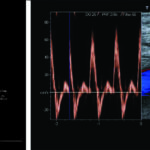

El análisis espectral representa el comportamiento de las arterias periféricas ante los eventos que ocurren en cada latido cardíaco, de manera tal que en él podemos reconocer claramente cuatro fases (Fig. 11).

Todas las arterias normales poseen el mismo examen espectral desde el nivel ilíaco hasta el nivel pedio (Fig. 12). Las velocidades y los calibres arteriales disminuyen a medida que nos acercamos a los niveles distales (Tabla 2).